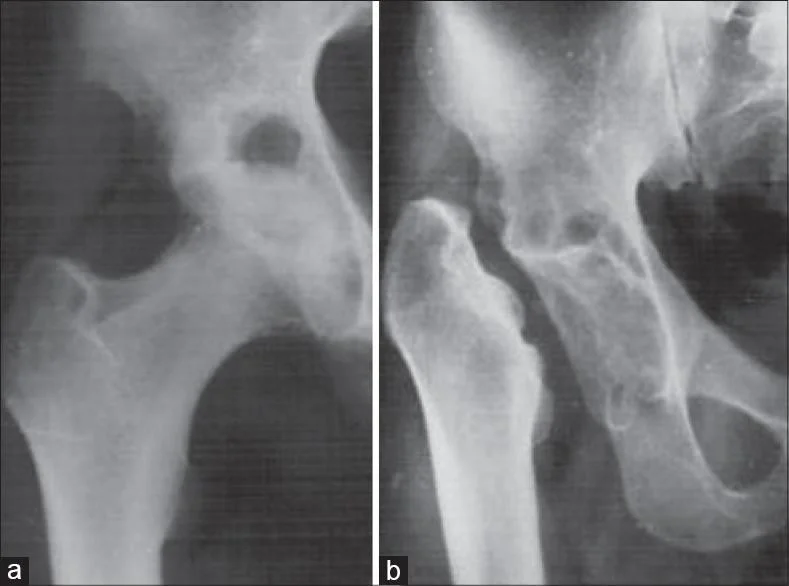

- Xray:

- AP & Lateral Weight-bearing views

- Pelvis:

- Standing AP pelvis

- Findings:

- Joint space narrowing

- Osteophytes formation

- Subchondral sclerosis

- Subchondral cysts

- loose bodies

- Deformity

Grading of Osteoarthritis

Kellgren-Lawrence (KL) grading scale

Radiographic Grading

The radiographic grading of osteoarthritis (OA) is as follows:

Grade 0 β No OA

Grade 1 β Doubtful OA

- Doubtful joint space narrowing, possible osteophytic lipping

Grade 2 β Mild OA

- Definite osteophytes, definite narrowing of joint space

Grade 3 β Moderate OA

- Moderate, multiple osteophytes, narrowing of joint, sclerosis and possible deformity of bone contour

Grade 4 β Severe OA

- Large osteophytes, marked narrowing of joint space, severe sclerosis and deformity of bone contour